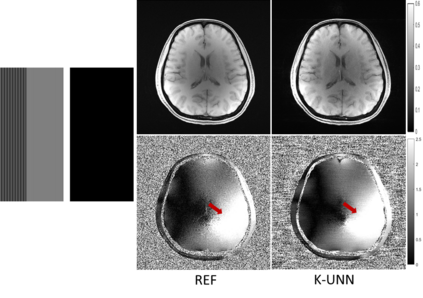

Recently, untrained neural networks (UNNs) have shown satisfactory performances for MR image reconstruction on random sampling trajectories without using additional full-sampled training data. However, the existing UNN-based approach does not fully use the MR image physical priors, resulting in poor performance in some common scenarios (e.g., partial Fourier, regular sampling, etc.) and the lack of theoretical guarantees for reconstruction accuracy. To bridge this gap, we propose a safeguarded k-space interpolation method for MRI using a specially designed UNN with a tripled architecture driven by three physical priors of the MR images (or k-space data), including sparsity, coil sensitivity smoothness, and phase smoothness. We also prove that the proposed method guarantees tight bounds for interpolated k-space data accuracy. Finally, ablation experiments show that the proposed method can more accurately characterize the physical priors of MR images than existing traditional methods. Additionally, under a series of commonly used sampling trajectories, experiments also show that the proposed method consistently outperforms traditional parallel imaging methods and existing UNNs, and even outperforms the state-of-the-art supervised-trained k-space deep learning methods in some cases.